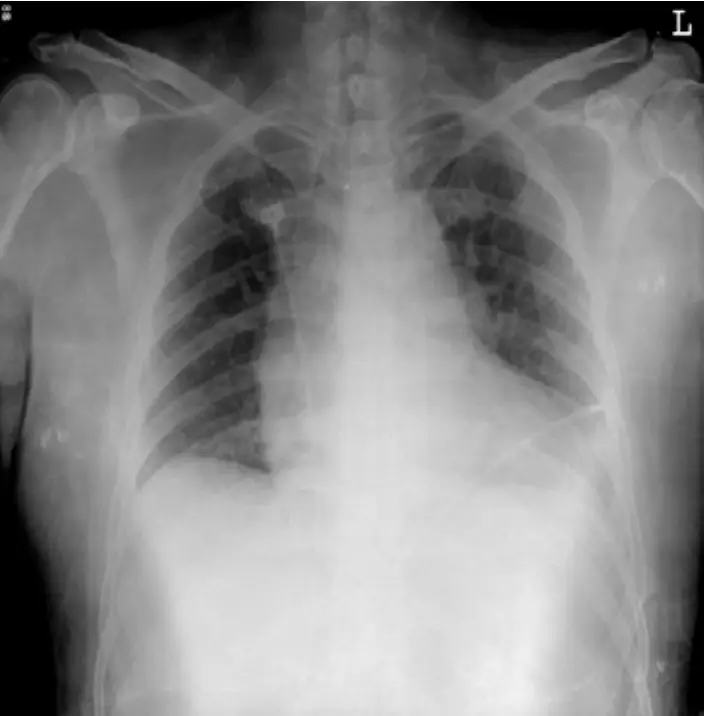

圖一:胸部X光(Chest X-ray,AP view)

本片為 AP 位胸部X光,最關鍵發現為縱膈明顯增寬(widened mediastinum),縱膈上端陰影向左側擴展,主動脈弓輪廓模糊,此為主動脈剝離的典型影像表現,約 60-90% 的主動脈剝離患者可見此變化。肺野無大量肋膜積液,無明顯肺水腫,心臟輪廓尚可辨別。